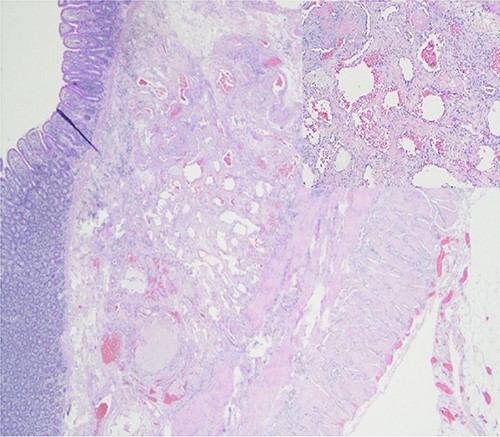

Further episodes of rectal bleeding were noticed the following day, and the hemoglobin level dropped significantly, requiring blood transfusions. An urgent computed tomography (CT) mesenteric angiography was performed, which demonstrated the extravasation of contrast in a segment of distal ileum (Fig. 1), ~30 cm from the ileocecal valve, suspicious for angiodysplasia. She subsequently underwent a laparoscopy, which was converted into a lower-midline laparotomy due to dense omental adhesions secondary to prior appendectomy and cesarean sections. After adhesiolysis, small bowel was thoroughly examined. The terminal ileum contained blood, while proximal small bowel appeared unremarkable. About 30 cm from the ileocecal valve, a small transmural lesion was noticed, which was red and blanching in appearance (Fig. 2). A segmental resection of ileum was performed, and the specimen was cut open to demonstrate the luminal aspect of AVM (Fig. 3). A primary anastomosis was performed. Histology showed a small, non- encapsulated nodule, composed of complex clusters of thin and thick-walled blood vessels, abnormally located in the submucosa (Fig. 4). Post-operatively, the patient had an uneventful recovery and was discharged home well after 4 days.